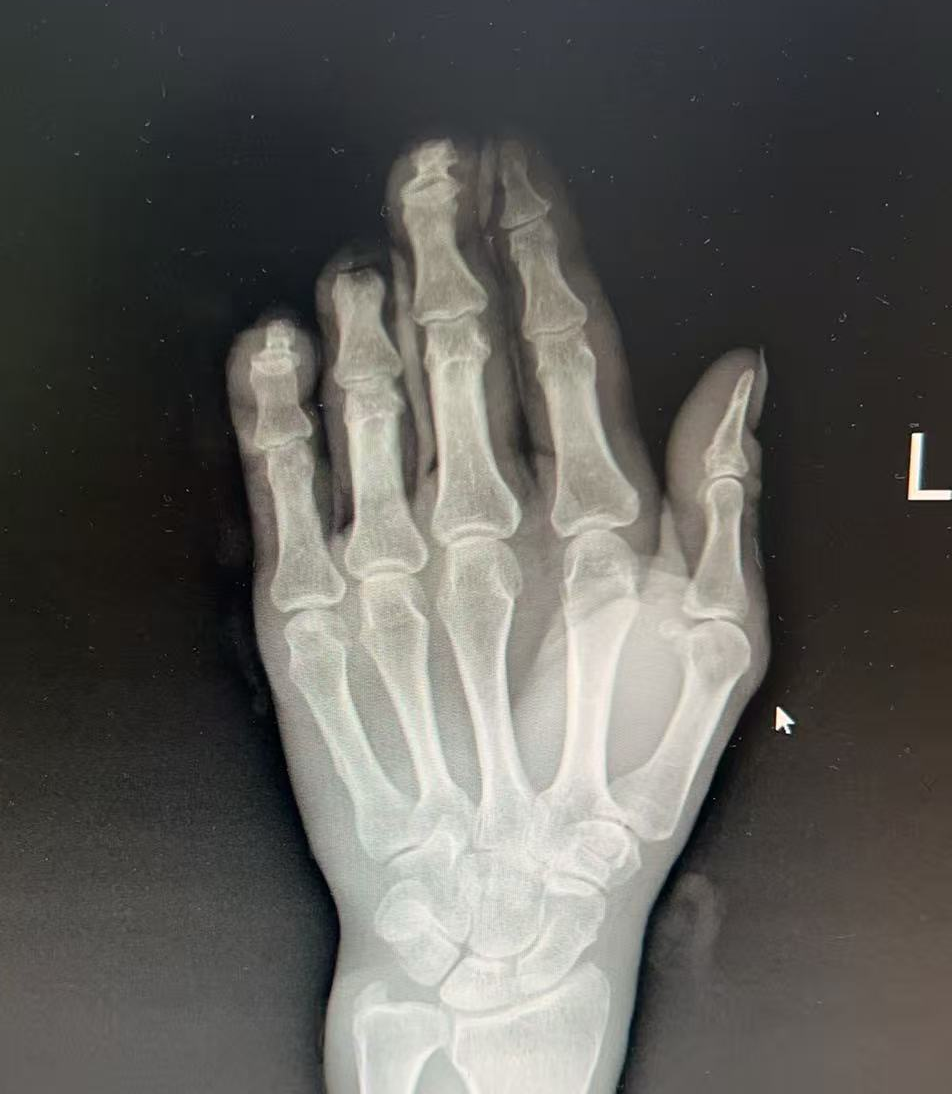

来到医院,老刘被诊断为“左环指末节完全离断;左小指两侧指固有动脉神经断裂;左中小指伸肌腱止点断裂”。

情况紧急,株洲市三三一医院骨伤关节病科团队迅速响应,为他制定了紧急手术方案。手术的关键在于在显微镜下,将离断手指的动、静脉血管、神经及肌腱一一吻合。

这是一场对眼力、手力和耐心的极致考验。经过3小时的精细操作,离断的环指血运成功恢复,颜色转为红润,宣告再植成功。同时,团队也对另外两根绞伤的手指进行了妥善的修复。手术顺利,患者离断的手指被成功接活,目前正在康复中。